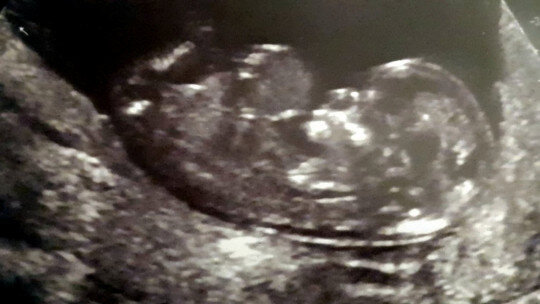

Belə ki, 6 iyun 2018-ci il tarixində, İngiltərənin Kembric şəhərində dünyaya gələn Lorel hələ ana bətnində, 12-ci həftədə olarkən dölə omfalosel (qöbək dəliyinin tam bağlanmaması və qarın içi orqanların göbək ciyəsinə qaçması) diaqnozu qoyulub.